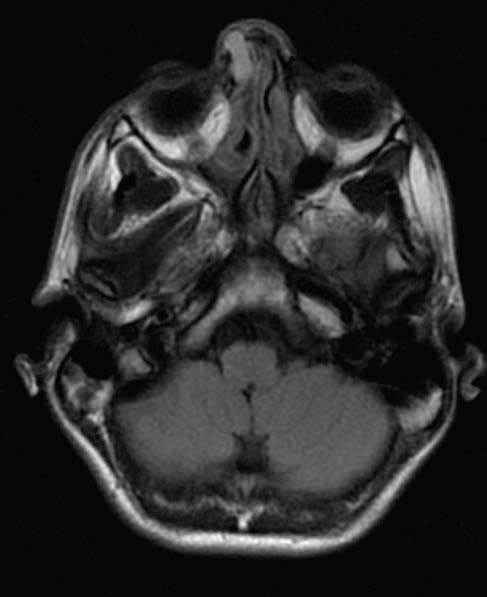

varicella-zoster virus infection

Jose Zayas, DO; Shannon Brockman; Ryan Baker, MD; Caitlin Wainscott, MD; Mobeen H. Rathore, MD

A 23-day-old boy presented with a 5-day history of worsening rash. The rash had begun as “red bumps” on his face.